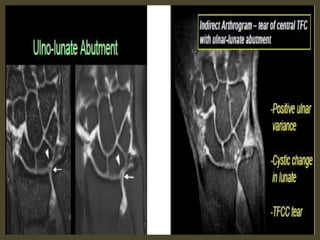

Volar intercalated segmental instability(VISI).

VISI with volar tilting of the lunate.

VISI with luno-triquetrum ligament tear and volar tilting of the lunate.

VISI deformity secondary to Lunotriquetral ligament tear.